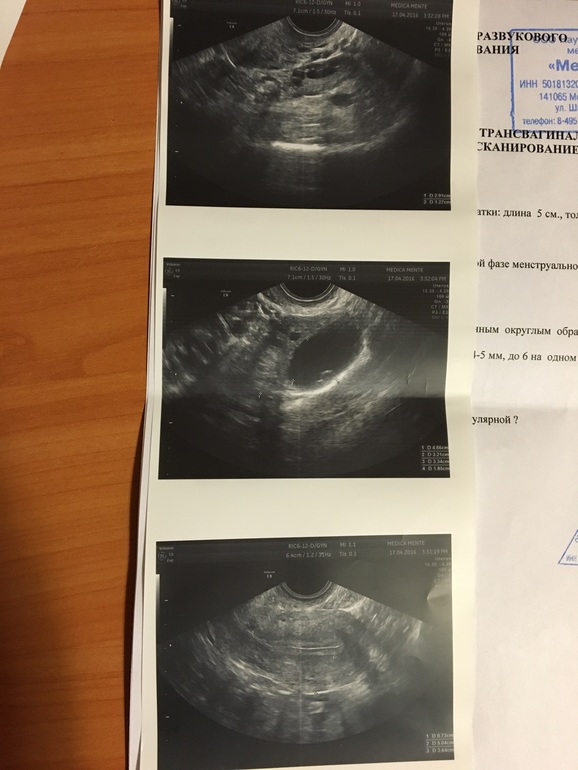

2 разных результата УЗИ

Короче я офигела за 2 дня у меня появилась миома, двурогая матка и эндометрий уменьшился на 2 мм!

Сказала, что мой врач ваще ничего не понимает и всё плохо, а у них типа крутой аппарат узи! Но на мой "непрофессиональный взгляд" первое узи 2 дня назад, как то правдоподобнее выглядит!

Прилагаю фото, какое на Ваш взгляд правдоподобнее?

второе фото не совсем информативно многое не написано, я бы больше поверила первомк фото.

да и жидкость является признаком овуляции, и кстати эндик после О может немного уменьшится, а потом снова начать ости это на фоне прогестерона происходит, меняется структура эндометрия

Второе фото мой врач, вся инфа в карте, большая часть на словах объясняется, заключение так для архива, по второму я верю что была О, т. к. Чувствовала ее вчера, но не более, даже по изображению на мониторах небо и земля! И сегодняшняя сразу стала рекомендовать себя свою клинику, оки и гомеопатию, как то не вызывает доверия(